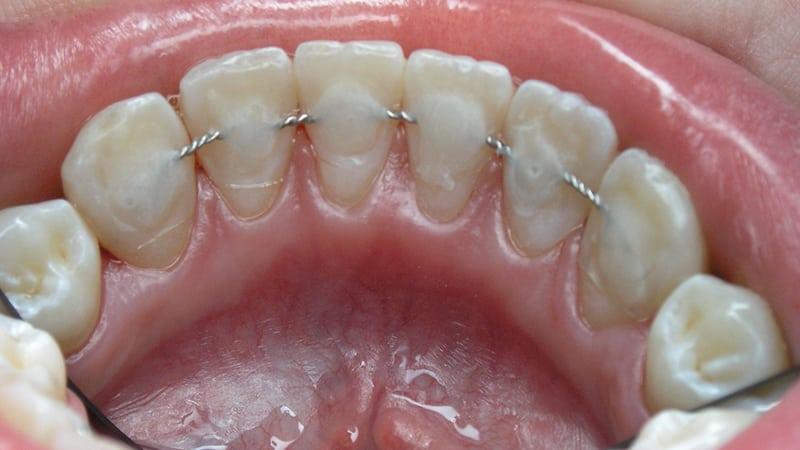

Если существует риск развития пародонтита, одних противовоспалительных процедур будет недостаточно. Чтобы предотвратить повторное воспаление и сохранить расшатывающиеся зубы, применяются специальные ортодонтические устройства – шины. Эти жесткие конструкции помогают зафиксировать зубы в правильном положении.